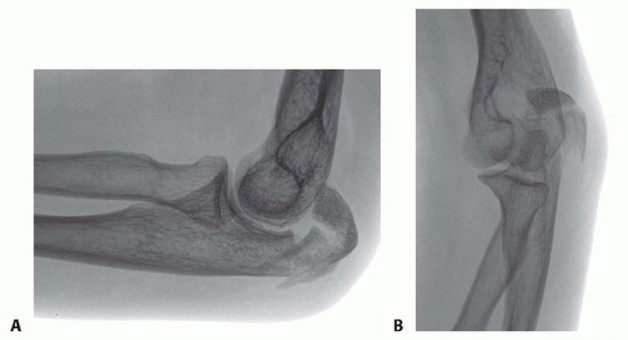

TECH FIG 1 • A. A lateral radiograph with the arm in plaster shows a transverse, noncomminuted fracture of the olecranon. B. An open reduction is held with a fracture reduction forceps. C. Two 1-mm Kirschner wires are drilled obliquely across the fracture site so that they exit the anterior ulnar cortex distal to the coronoid process. (A,B: Copyright , MD.)